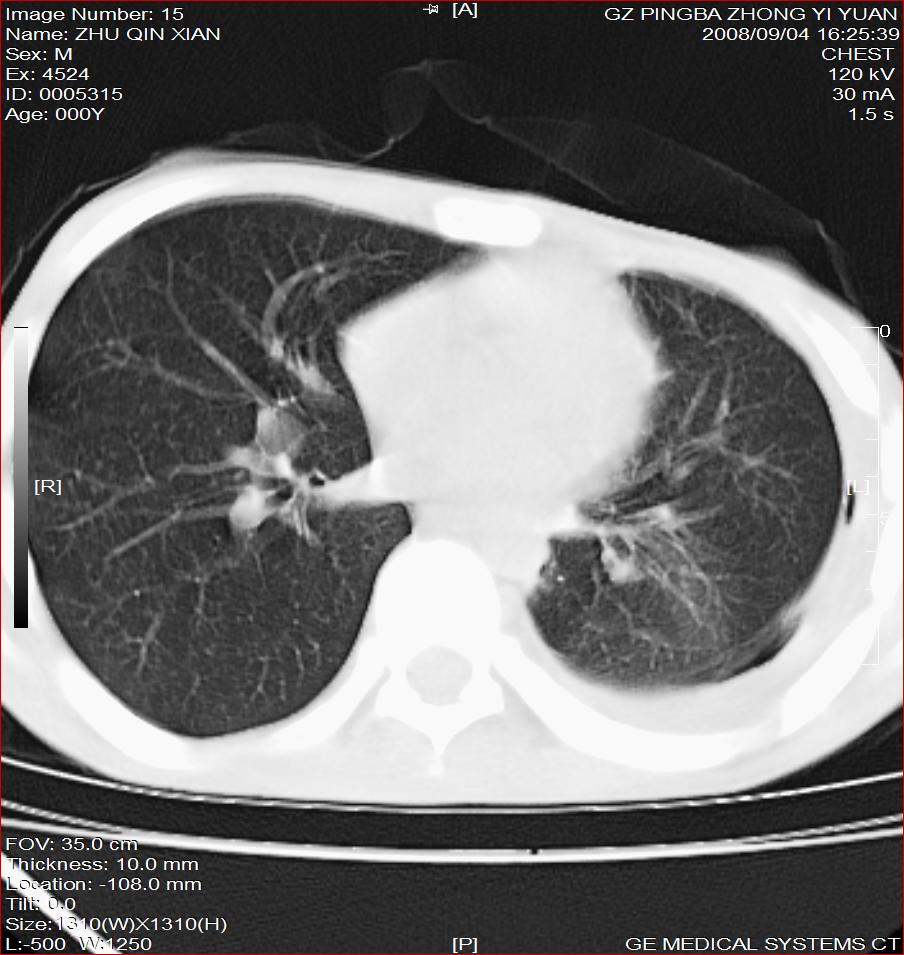

以下是引用随光逐影在2008-9-4 20:05:00的发言:[br]1)考虑两肺结核。2)左侧胸膜炎(胸膜肥厚、粘连,胸腔积液)。3)左侧局限性气胸。

以下是引用子十在2008-9-4 19:34:00的发言:[br]左上肺结核并空洞及双肺播散。节段性肺不张、胸腔积液、胸膜肥厚粘连。[br]